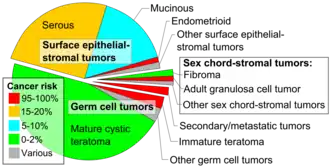

Sex cord–gonadal stromal tumour is a group of tumours derived from the stromal component of the ovary and testis, which comprises the granulosa, thecal cells and fibrocytes.[1] In contrast, the epithelial cells originate from the outer epithelial lining surrounding the gonad while the germ cell tumors arise from the precursor cells of the gametes, hence the name germ cell.[1] In humans, this group accounts for 8% of ovarian cancers and under 5% of testicular cancers. Their diagnosis is histological: only a biopsy of the tumour can make an exact diagnosis. They are often suspected of being malignant prior to operation, being solid ovarian tumours that tend to occur most commonly in post menopausal women.

This group of tumours is significantly less common than testicular germ cell tumours in men,[2] and slightly less common than ovarian germ cell tumours in women (see Ovarian cancer).[1]